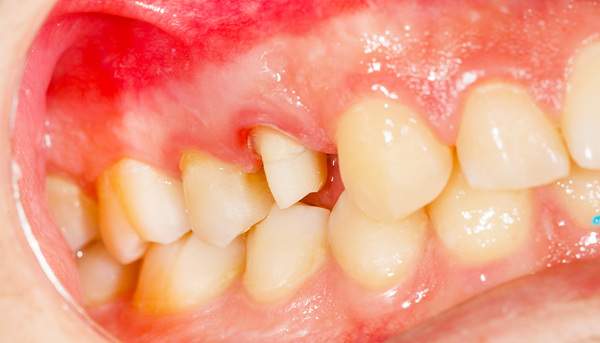

BEFORE

歯周病症例の治療前

黄色:歯の根本に黒い歯石が付着しているのがわかり

ます。

青色:歯にプラークが付着していると、歯の周りの歯ぐきに炎症があり、赤く腫れているのがわかり